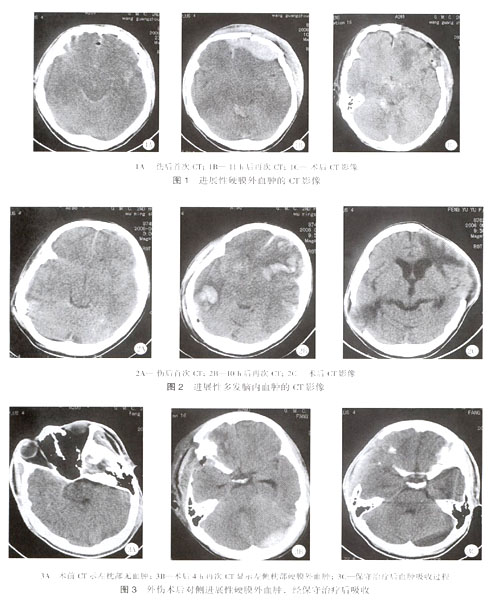

脑挫裂伤